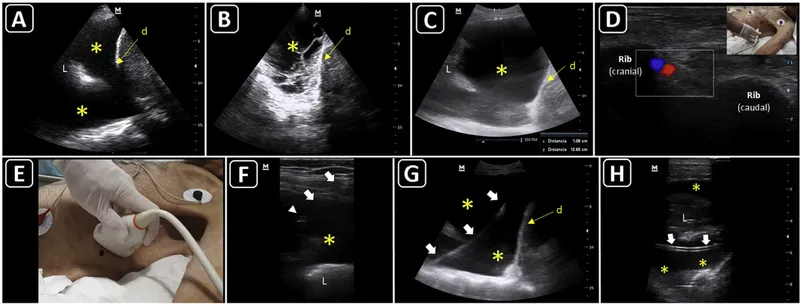

- Thoracentesis (Pleural Effusion)

⭐ For thoracentesis, needle insertion is 1-2 ICS below fluid level (mid/post-axillary line), above the rib to avoid neurovascular bundle.

- Paracentesis (Ascites)

- Liver Access (e.g., Biopsy, Drainage):

- Spleen Access: